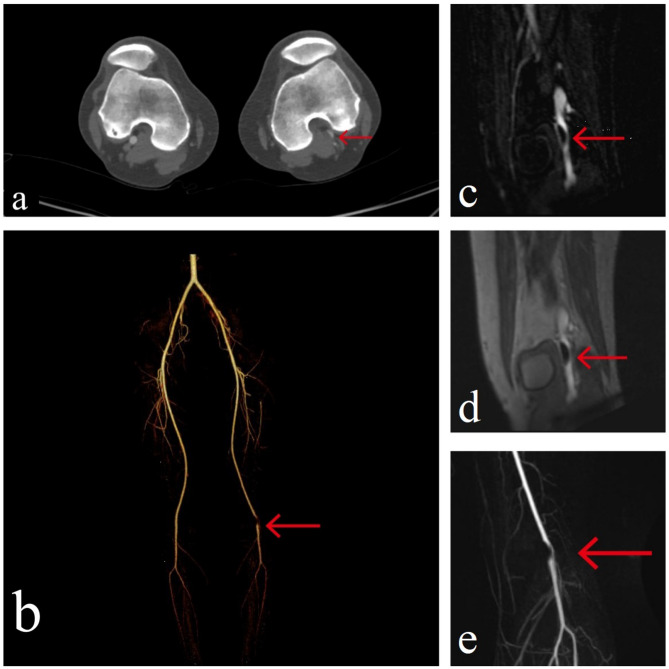

Case presentation: This case describes a 36-year-old female who presented with sudden left lower limb soreness that worsened with activity over five days, but without symptoms such as intermittent claudication or rest pain, which are typically associated with other vascular diseases. The patient had no significant history of smoking or other risk factors for peripheral arterial disease. Imaging studies, including angiography, revealed a focal filling defect and luminal narrowing in the popliteal artery (PA), which suggested the presence of an abnormality in the vessel wall. Given the findings and the patient's symptoms, surgical intervention was planned. The procedure involved the resection of the affected portion of the artery and replacement with an autologous vein graft. Pathological examination of the resected arterial segment confirmed the diagnosis of CAD, revealing a cyst in the adventitia filled with a gelatinous substance.